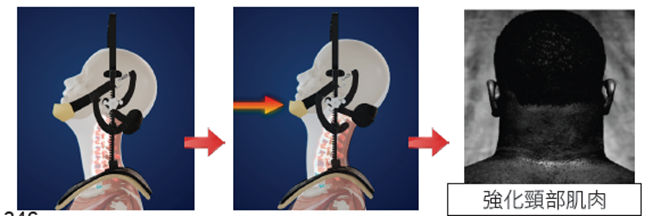

要配合做下巴後收運動鍛鍊(Chin Tuck Exercises) 強化鈄方肌,支撐頭部,防止頸椎不穩,避免頭頸容易體位移動或扭傷。若不佩戴強力後枕頸椎牽引器,單獨做下巴後收運動鍛鍊時,頸椎不夠穩定,不夠安全。